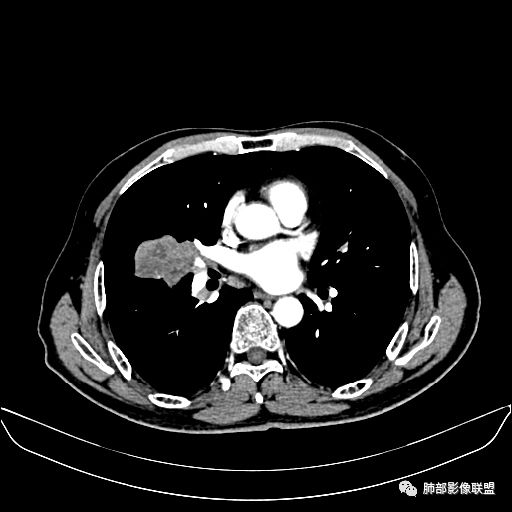

动脉期

老年男性,因“咳嗽咳痰1月余。”入院。病程中咳嗽咳痰,咳黄白痰,间断咯少许鲜红色痰血。PPD阳性。胸CT:右肺中叶外侧段支气管管腔阻塞,大片实性病变,病灶边缘光滑,部分边缘膨隆,可见分叶,肺门及纵隔可见肿大淋巴结,并可见钙化。增强可见病灶明显强化,而且延迟强化明显,病灶内多发低密度区,内见血管影,血管变细、部分血管破坏。考虑恶性病变可能性大,鉴别慢性肉芽肿性病变。

胸CT:跨叶大肿块,主体在中叶,右中叶外侧段支气管阻塞,病灶部分边缘膨隆,可见分叶,部分边缘平直,肺门及纵隔可见肿大淋巴结。增强病灶不均匀强化,延迟强化明显,病灶内多发低密度区,内见血管飘浮,部分血管变细、模糊。考虑:恶性病变可能性大,大细胞?淋巴瘤?鉴别慢性肉芽肿性病变。

右肺中叶软组织肿块,外围向内生长,叶间胸膜向前内移位,肿块近肺门侧跨叶,中叶外侧段支气管截断,密度不均匀,双侧肺门及隆突下见肿大淋巴结,增强后呈中度不均质强化,肺动脉供血,多发坏死区,边界尚清,坏死区域内见结构,结合病史考虑恶性,鉴别诊断1结核,爬行征是沿支气管树分布,外宽,内窄,周围有卫星灶,内气管狭窄后扩张,此例沿叶间胸膜长轴分布,气管有截断,不典型。2炎性肉芽肿,符合的地方下方层面增强后延迟性轻度环形强化,不符临床无发热等急性感染病史,实验室指标不符,病灶周围渗出及慢性炎性改变有,不明显。

吴婧老师和南边老师都对该病例进行了深入分析。从支气管管壁的增厚,支气管狭窄后扩张,支气管粘液栓,病灶形态,到病灶不均匀强化及坏死彻底,到周边病灶及肺组织空气的潴留,加之纵隔内淋巴结肿大伴钙化等等,都支持慢性炎性病灶,尤其是结核。

墨西哥仙人掌征---结核        影像上结核灶,粗大的均匀枝干,推测是支气管囊状扩张引起的,在非支气管区,形成圆形坏死囊群;如果这些坏死比较稀薄,又遇到扩张支气管,就会形成粗大的“墨西哥仙人掌”。结核引起的支气管近端炎症纤维化,可以造成支气管阻塞,从而将干酪样坏死物封堵在管腔内。仙人掌主干内部应该是干酪为主,稀薄的,具有流动性,时间久了会出现钙化。

结核坏死与鳞癌鉴别有一点是结核坏死没有方向性,鳞癌有。鳞癌靠近支气管近端部分,血供容易维持,不易坏死,所以坏死靠外侧。而结核干酪样坏死,把一定体积的流动性坏死物,包裹起来,什么形状最省料?坏死物包裹,表面积最省的自然是圆球形,而遇到支气管,坏死物一多,就把支气管撑大了。包裹物是就地取材,扩张的支气管就成了包裹结构。